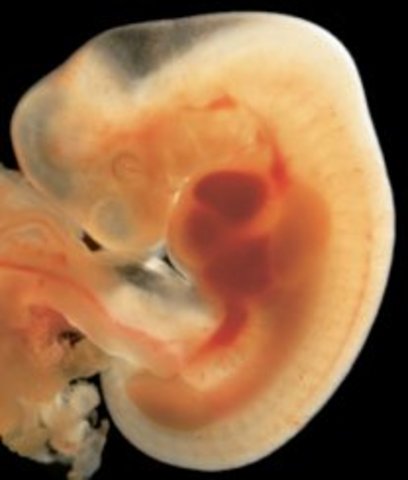

• week6

week6

1.The first blood cells and blood vessels are developing

2.heart is formed and begins to beat

3.At this time the embryo is still smaller than the size of a raisin

4.The spine and spinal cord grows faster than the rest of the body at this stage and will give the appearance of a tail

• week7

week7

1.Arm and leg buds begin to grow.

2.The heart is beating with one chamber

3.A dividing wall is formed in the heart

4.The baby's eyes and inner ears are starting to develop

5.the brain is growing